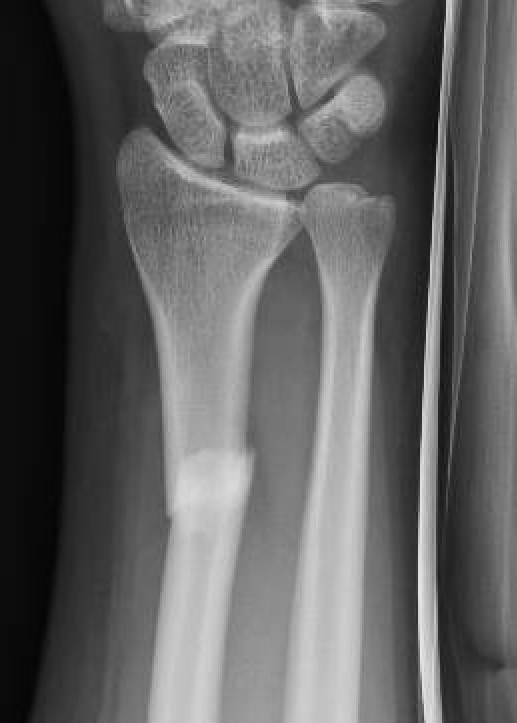

Xray

DRUJ disruption

- widened space between radius and ulna on AP

- dorsal subluxation / dislocation of ulna on lateral

- radial shortening > 5 mm

- ulna styloid fracture

Widening of interval between radius and ulna / clear disruption of DRUJ